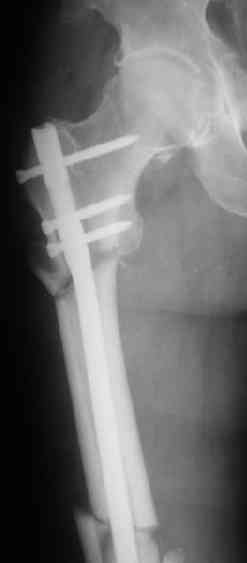

Вот несколько. С тисками и трубой на днях сделаем.

> Вот несколько. С тисками и трубой на днях сделаем.

Саша, последний штифт, пожалуй, перегнули?

> Саша, последний штифт, пожалуй перегнули?

Там заход сделан как для прямого штифта, не через вертел.